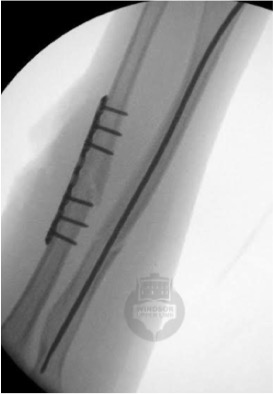

Image opposite - intra-operative x-rays of a child's forearm fracture. The ulna has been plated, but the radius has been fixed with a flexible titanium nail